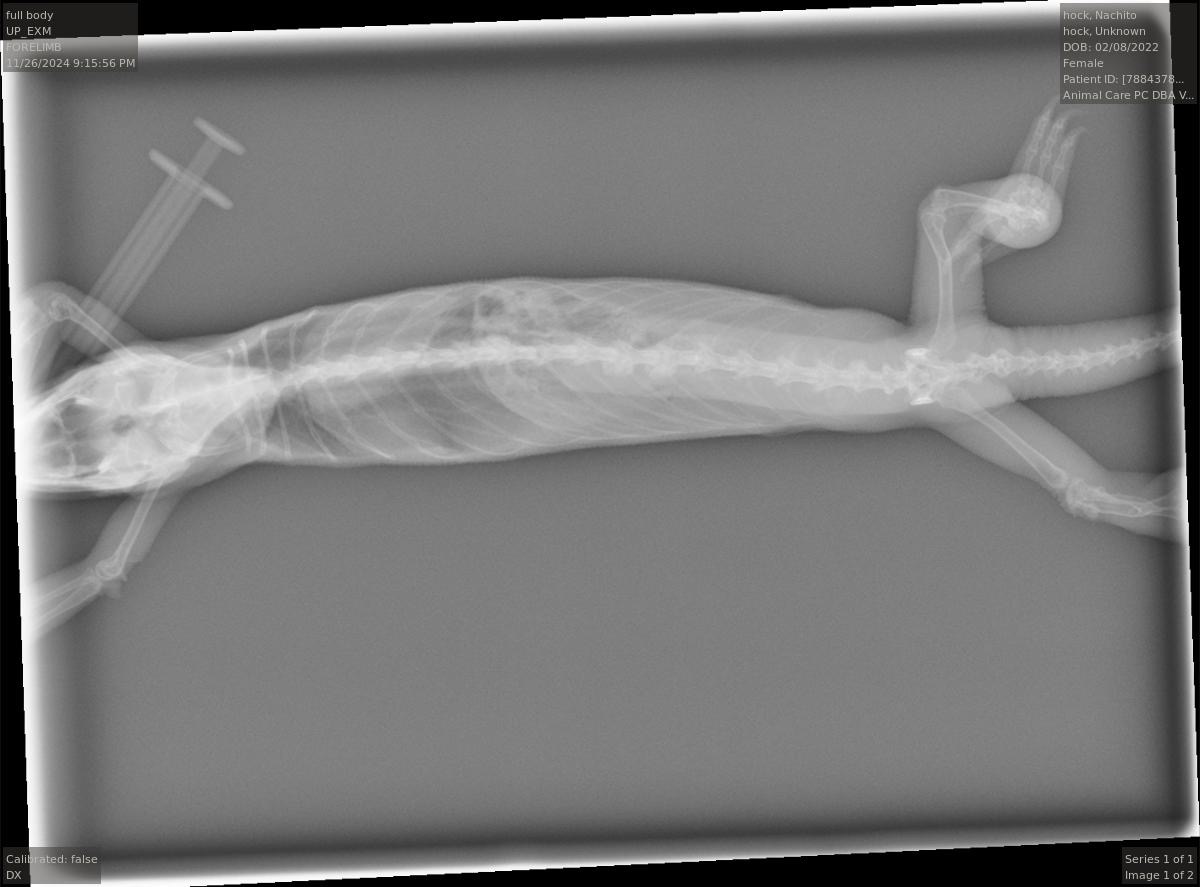

! But today at a vet appointment, Nachito was finally diagnosed with gout. After months of her uric acid levels seeming to be normal, today they came back as elevated.

The lump on her elbow was removed, apparently it was a clogged pore? So we will be keeping an eye on that!

And apparently the follicles were hard to find on ultrasound and the doctor doesn’t really know what going on with them. She didn’t think they were reabsorbed, but Nachito has gone down is weigh a little so maybe they are squished in there and hard to see?

Other than the uric acid levels and pore, the vet said there was nothing else significant on the X-rays and ultrasound.